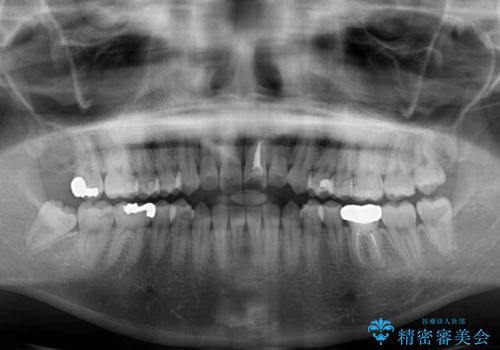

- 口元の膨らみが気になるとのことで来院された患者様です。

非抜歯で口元の突出感を少し改善させる治療も提案しましたが、最大限口元を引っ込めたいとのことでした。

上下左右第一小臼歯4本を抜歯し、ワイヤー装置により矯正治療を行うこととしました。